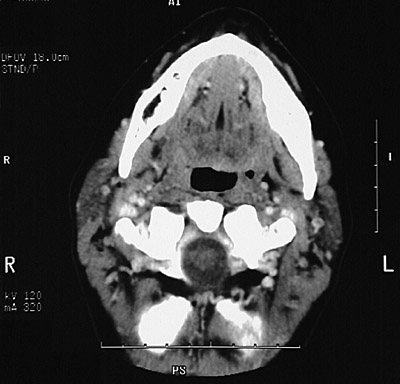

This is a normal axial head and neck CT scan demonstrating the mandible and oropharynx and tongue and facial vein and parotid gland and sternocleidomastoid muscle and internal jugular vein and external carotid artery and internal carotid artery and retromandibular vein.